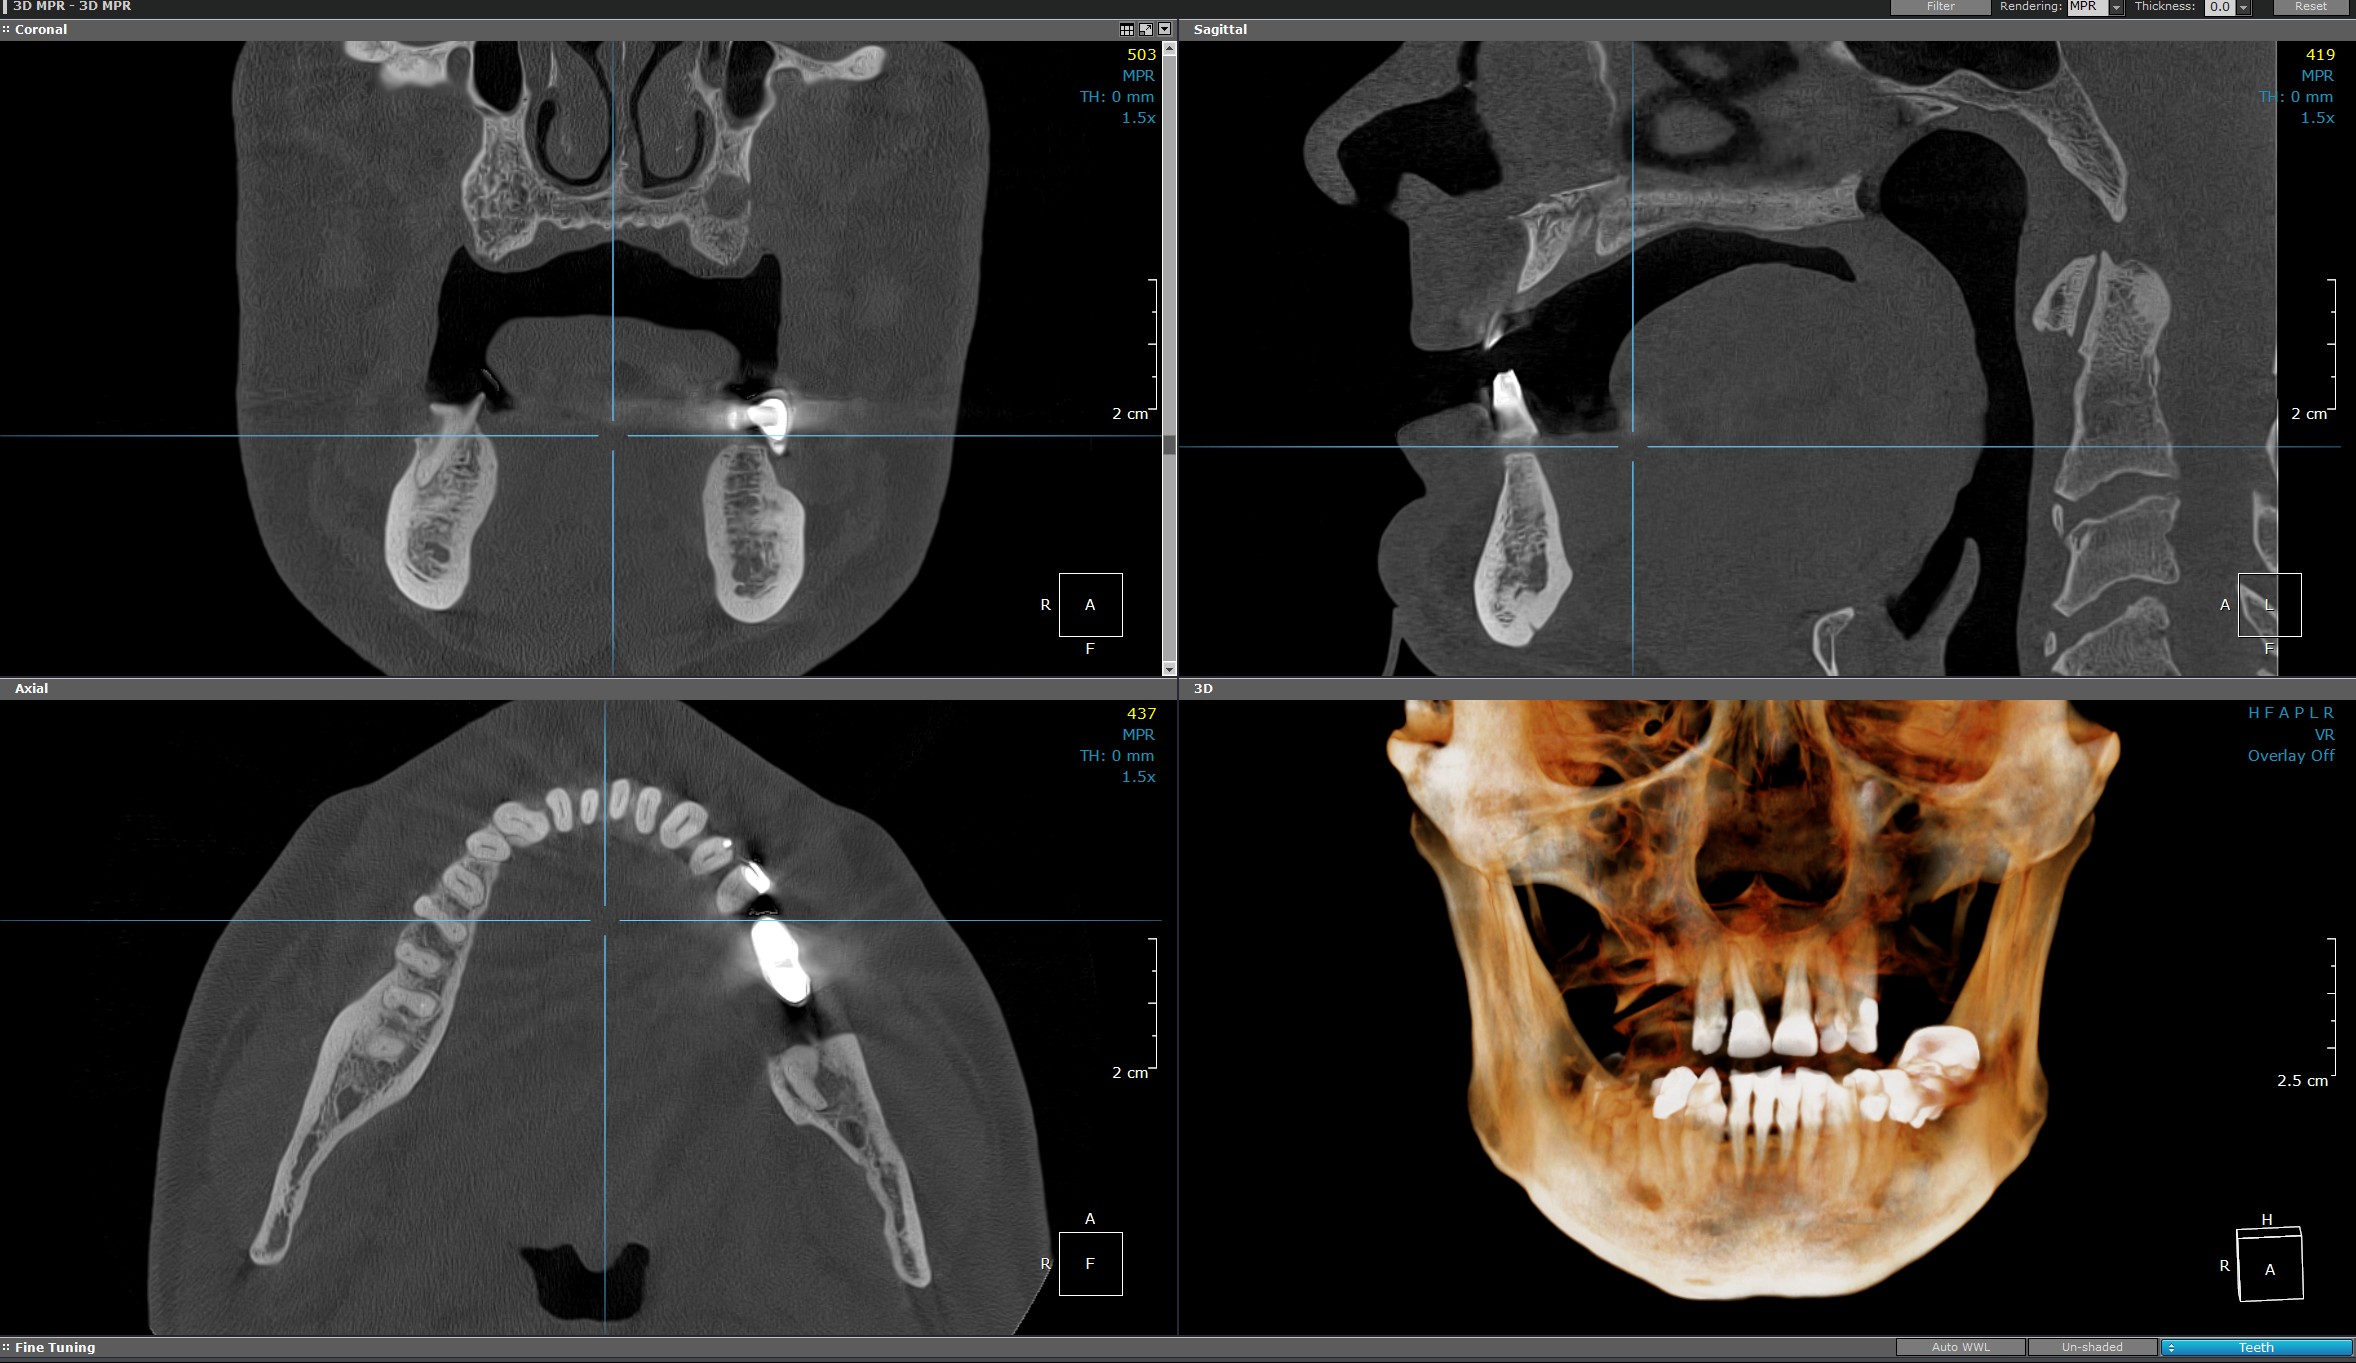

Spre deosebire de radiografiile 2D tradiționale, care oferă doar o imagine plană, radiografia 3D (CBCT) furnizează o reprezentare tridimensională a structurii osoase, dentare și a țesuturilor învecinate.

Această tehnologie permite medicului stomatolog să observe toate detaliile din unghiuri multiple, cu o acuratețe superioară.

CT maxilar/mandibular sau bimaxilar (Computer Tomograf)

Furnizează imagini detaliate și precise cu privire la structurile dentare maxilare sau mandibulare, esențiale pentru diagnostic și planificarea tratamentelor dentare complexe.

Procedura este rapidă, non-invazivă și nedureroasă, folosind o tehnologie avansată de scanare.

Aceasta este utilizată la evaluarea preoperatorie a osului maxilar, planificarea implanturilor dentare și la stabilirea densității osoase, detectarea fracturilor, tumorilor, a infecțiilor și raportului acestora cu structurile anatomice învecinate acestora